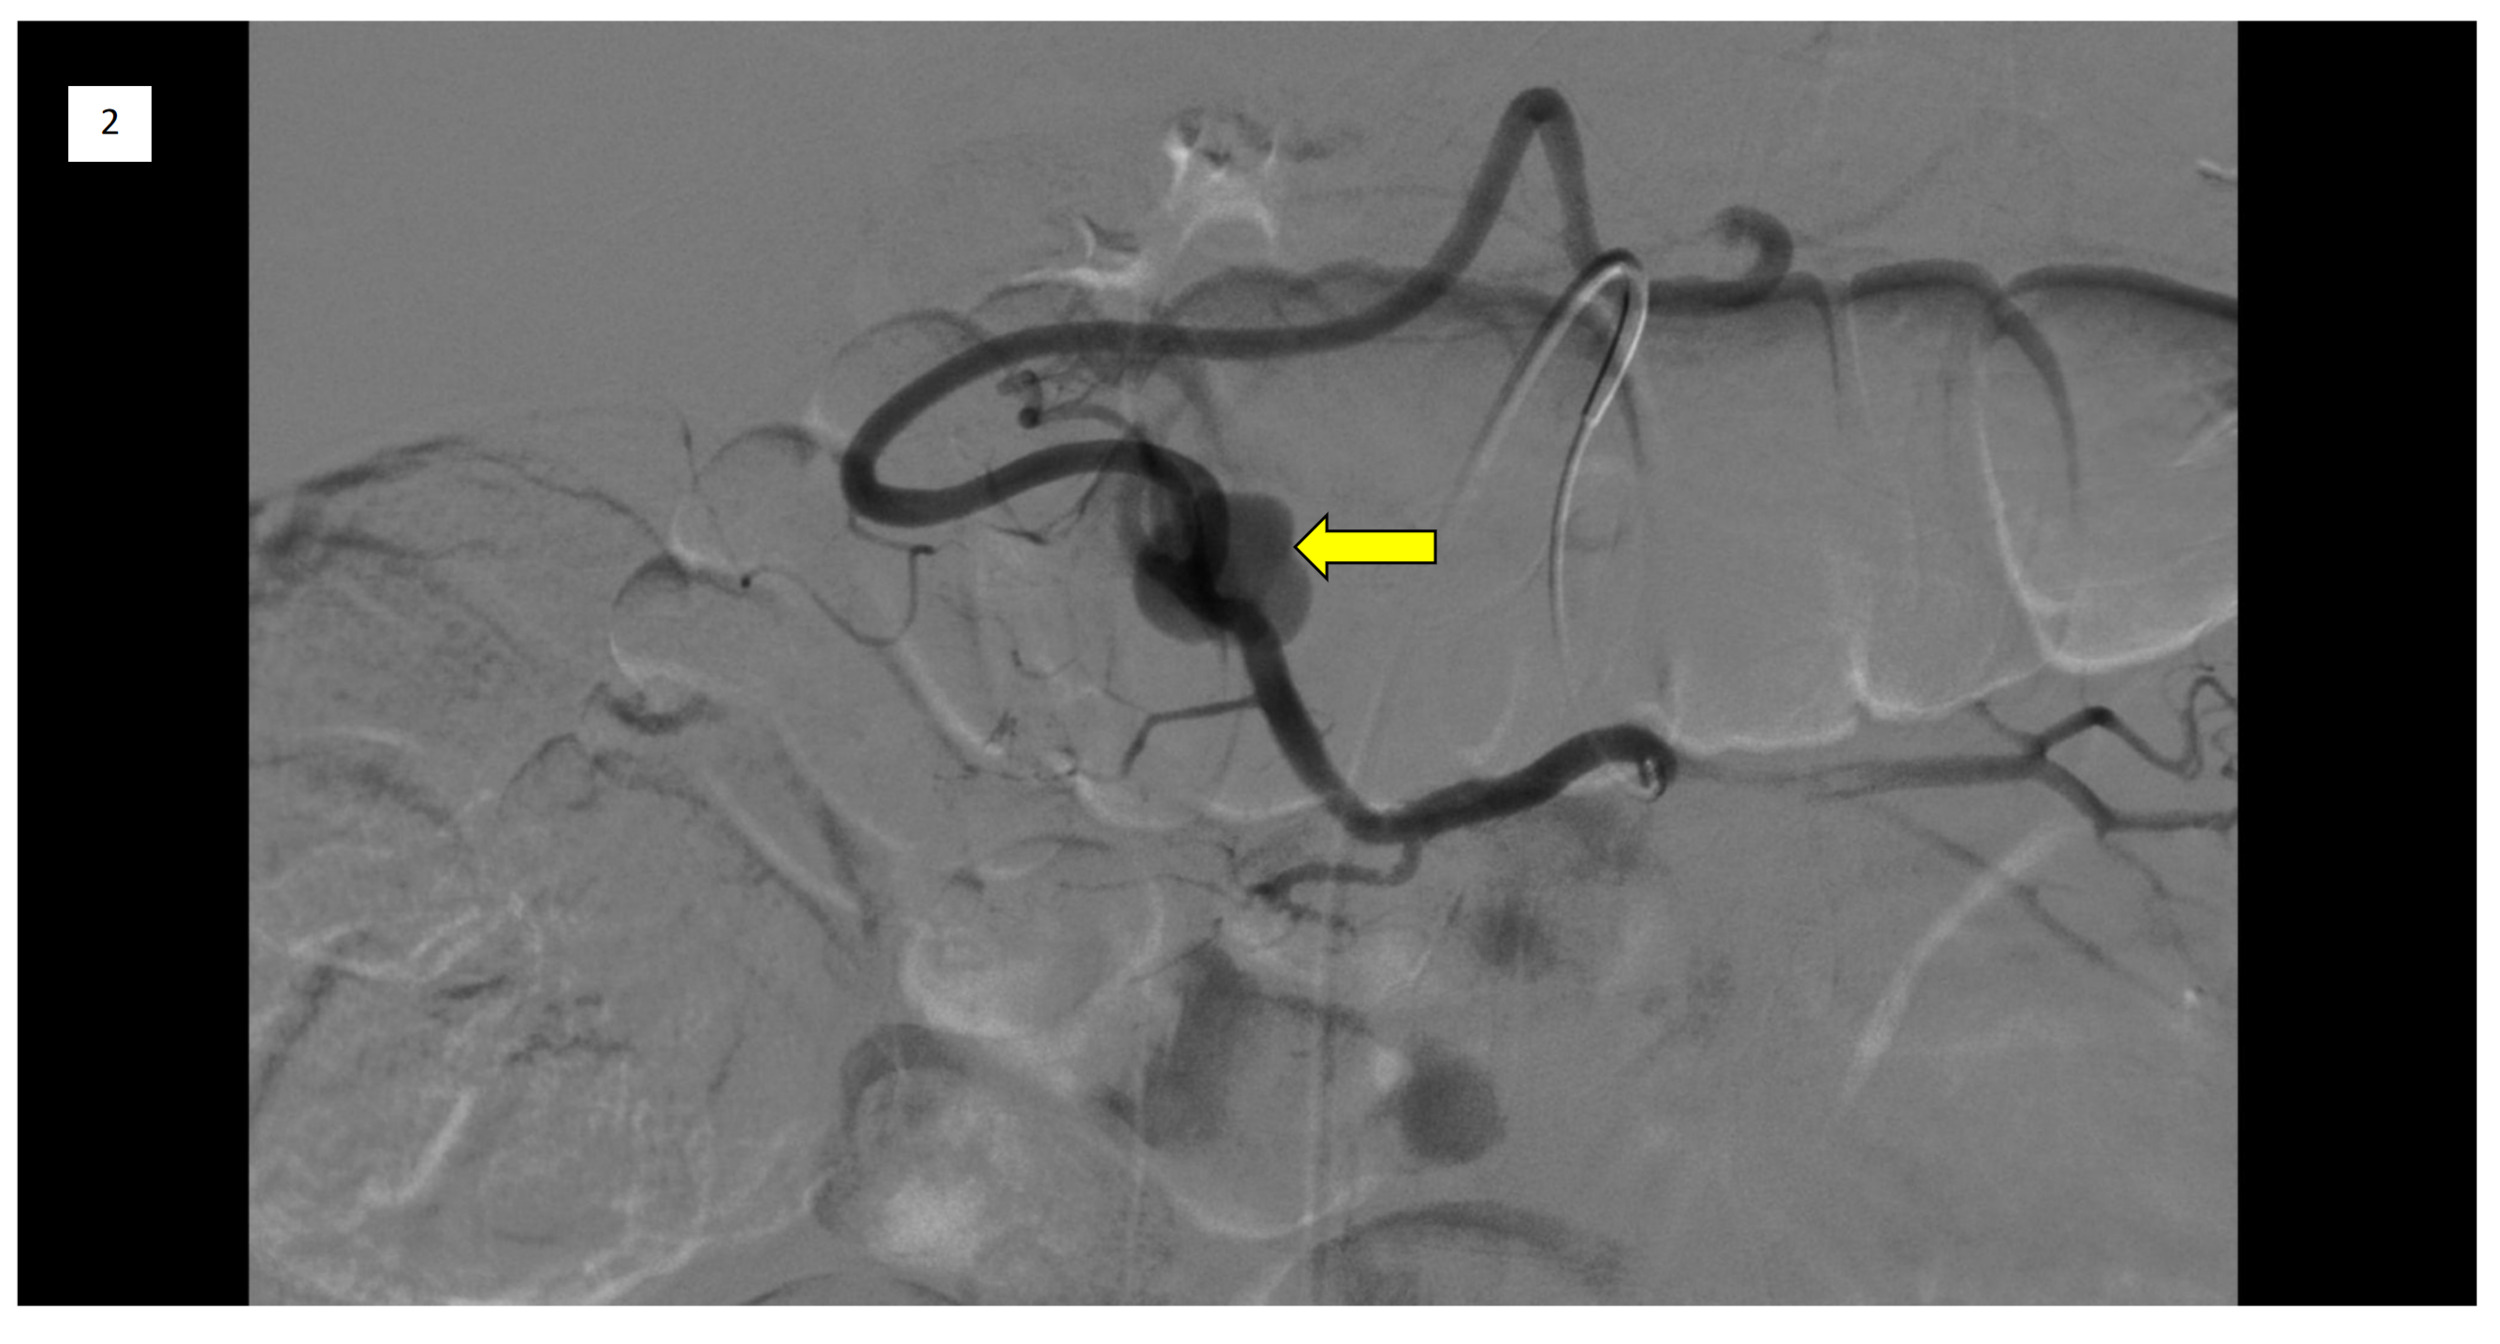

On day 1, the immediate management required 2 units (560 mL) of packed red blood cell transfusion. Further evaluation with a contrast Computed Tomography (CT) scan of the abdomen to identify the source of bleeding revealed a heterogeneous lesion along the pancreatic head and uncinate process, measuring approximately 4.1 x 3.7 cm. There were multiple enhancing foci along the mass-like structures, the largest measuring 1.6 x 0.9 cm. Similar lesions were noted in the pancreatic head and tail, suggesting sequelae of chronic pancreatitis. Gastroenterology was consulted. After stabilization, on day 2, the patient underwent upper gastrointestinal endoscopy (UGIE) with endoscopic ultrasound (EUS). The EUS showed findings suggestive of chronic pancreatitis with multiple cysts, and the UGIE showed active bleeding from the ampulla of Vater [Figure 1a] and subepithelial prominence of the duodenal bulb [Figure 1b], likely from the pancreatic pseudoaneurysm.